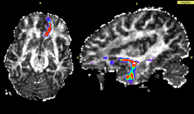

| − | [[Image:OFC.png|thumb|left|200px|Figure | + | [[Image:OFC.png|thumb|left|200px|Figure 2: Stochastic tractography connection between OFC and amygdala]][[Image:Cingulate_gyrus.jpg|thumb|left|200px|Figure 3: stochastic tractography reveals anatomical connection between anterior and posterior cingulate gyrus activated during fMRI Color Stroop task]] |

- Since diffusion direction uncertainty within the gray matter is quite significant; principal diffusion direction approaches usually do not work for tracking between two gray matter regions. Thus if one requires finding connections between a priori selected anatomical gray matter regions, defined either by anatomical segmentations (in case of using structural ROI data), or functional activations (in case of megring DTI with fMRI), stochastic tractography seems to be the method of choice. Here is an example of this application to anatomical data (Figure 2) and to fMRI data (Figure 3).